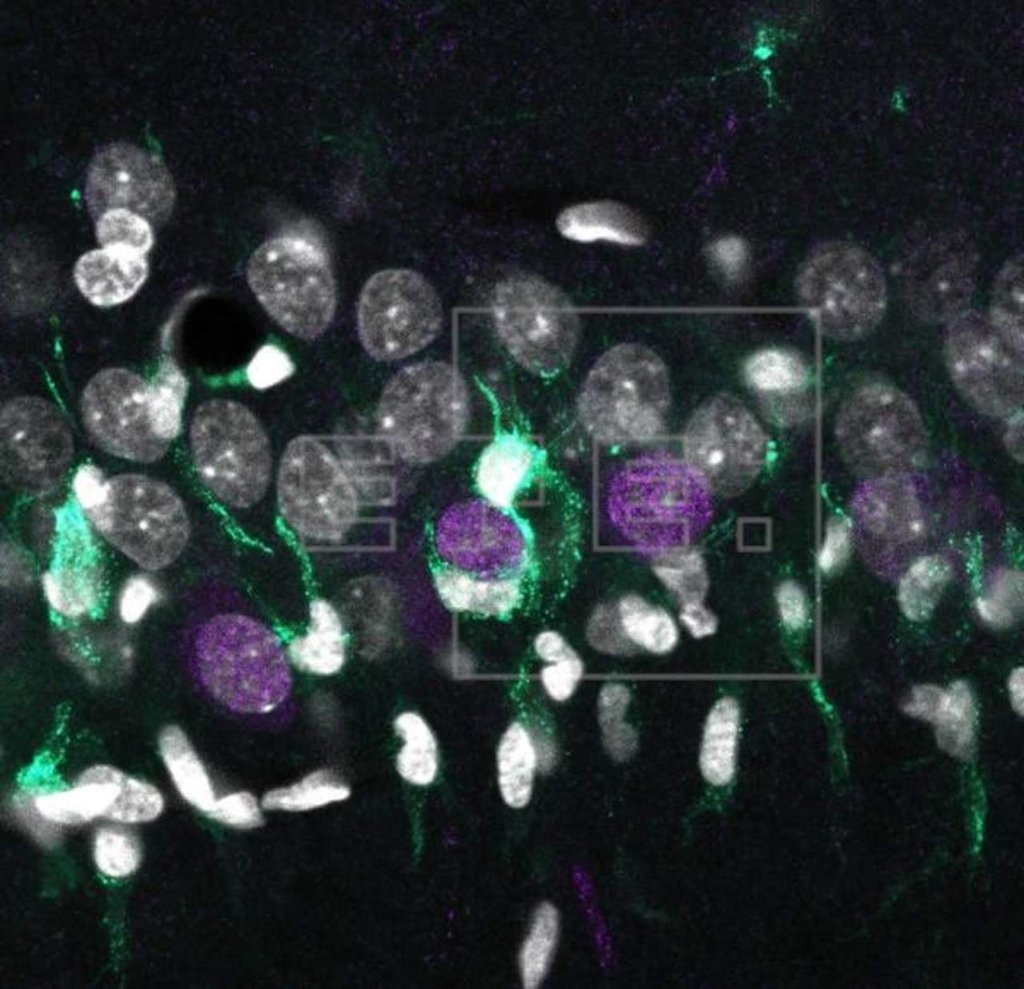

El equipo descubrió que esa atrofia se caracteriza por la muerte de una población de neuronas denominadas piramidales en la capa superficial de la región CA1 del hipocampo, una zona implicada en la formación de la memoria.

Los mapas genómicos intentan asignar diferentes genes con elementos biológicos concretos. En el caso del cerebro, "se trata de vincular una serie de genes con tipos neuronales específicos, como las neuronas, los astrocitos y la microglía", explica Liset Menéndez de la Prida, del Instituto Cajal del CSIC.

El estudio se basó en análisis genómicos, histológicos y electrofisiológicos, que permitieron comprobar cómo la capa superficial de la región CA1 del hipocampo "es más vulnerable y tiene más propensión a degenerar que la capa profunda".

Por el perfil de expresión génica de cada célula identificaron genes que se expresan de manera muy diferente en los distintos tipos celulares de esta región del hipocampo.

Dos procedimientos avanzados para la toma de muestras biológicas: la micro-disección láser de una región del tejido cerebral y el muestreo de núcleos de células individuales extraídos de rata y ratón, junto con técnicas bioinformáticas han permitido identificar las firmas genéticas de la neurodegeneración.

Cuando las neuronas comienzan a degenerar, emiten señales que son captadas por la microglía (las células inmunes del cerebro). Cada uno de estos procesos lleva aparejada la activación o desactivación de determinados programas genéticos, que son los que constituyen la firma genética, destaca José López-Atalaya, del Instituto de Neurociencias UMH-CSIC.

Los investigadores registraron la actividad eléctrica de las neuronas individuales y comprobaron que algunas mostraban signos de hiperexcitabilidad, característicos de la epilepsia, en especial las neuronas piramidales, que están localizadas en la capa superficial de la región CA1 del hipocampo.